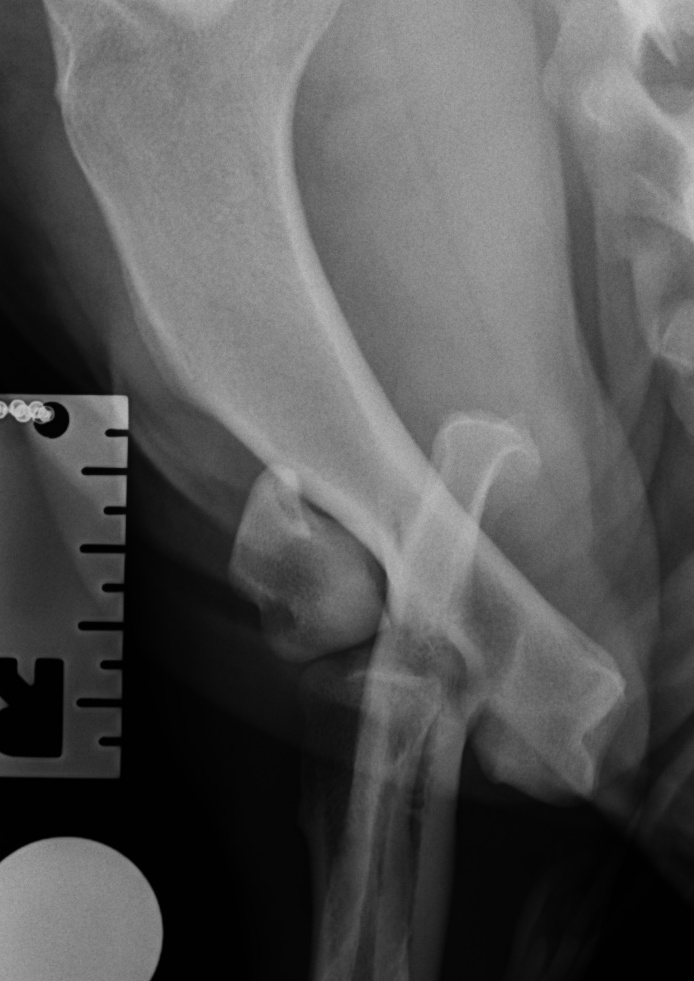

Humeral condylar fractures are a common sort of broken bone that effects the elbow in the front leg of dogs and cats. They most commonly occur in puppies between 12 and 16 weeks of age. Sometimes they occur in younger animals, and in adults they are most commonly seen in Spaniels as a consequence of humeral intracondylar fissure (HIF). They are articular fractures, which means that they involve the joint surface and should be treated promptly with surgical fixation.

Effected dogs suddenly become very lame on the leg, and might stop using it altogether. However, the lameness can improve quite quickly in some dogs, and these fractures occasionally go undiagnosed for some days or even weeks. This can make them very difficult to repair, as bone heals quickly in puppies. But the elbow joint is left in a very abnormal shape if they heal in the wrong place, and long-term function can be poor if they are not treated surgically.

Radiographs (x-rays) are usually enough to make a diagnosis and plan surgery. However, especially in adult dogs, a CT scan is a good idea to check the other elbow for signs of HIF.

These fractures need to be re-aligned as accurately as possible, within a few days of occurring, to try and optimise elbow function in the long term. They are generally stabilised using a screw across the condyle, and a plate and screws running up the side of the bone. Sometimes, the plate is not used and more screws or a bone pin is used instead. Movement Specialist, Ben Walton, helped to design and develop a system of anatomic bone plates for humeral condylar fractures.